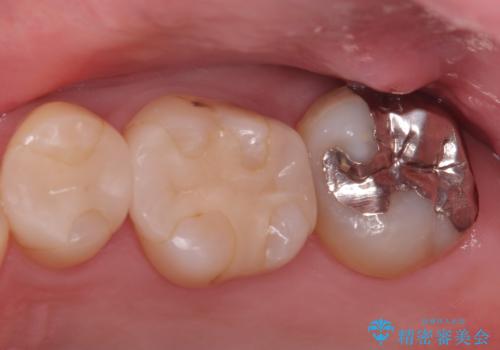

【セラミッククラウン】インレーの下の大きな虫歯

- レントゲンにて昔入れたインレーの下に虫歯が見つかった患者様です。

歯髄に近接する虫歯でしたが、根管治療は必要なくクラウンにて修復を行うことができました。